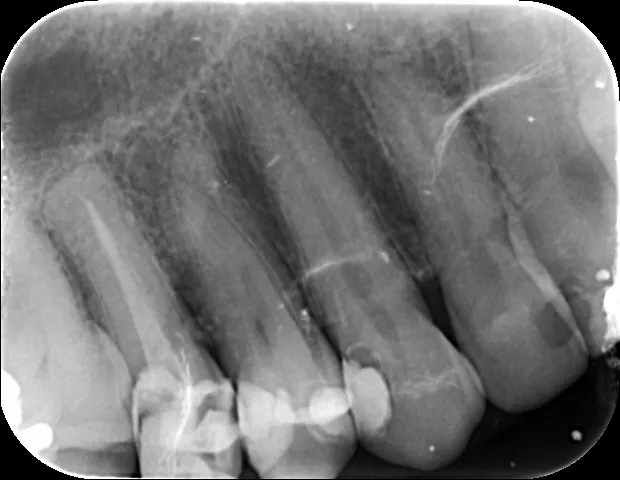

Son imágenes pequeñas que se toman dentro de la boca del paciente en el mismo gabinete. Se utilizan para diagnosticar caries interproximales o problemas con la raíz de los dientes.

Las radiografías intraorales se utilizan para ver la estructura (raíz y corona) de uno o dos dientes.